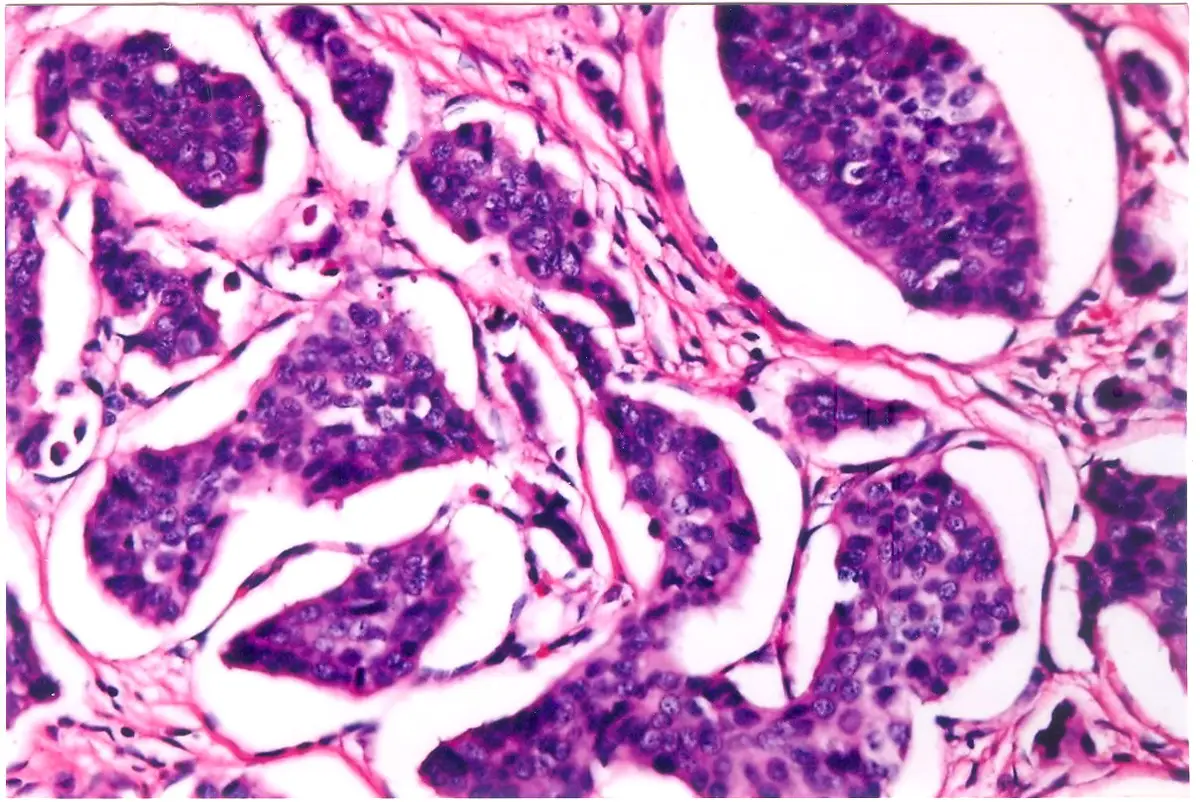

附圖為一張組織病理切片的顯微鏡照片(H&E染色):

1. 低倍/中倍視野觀察:影像顯示腫瘤細胞排列成巢狀(nests)、島狀(islets)或樑狀(trabeculae)結構,被纖細的纖維血管基質(fibrovascular stroma)所分隔。這是神經內分泌腫瘤典型的**器官樣(organoid)**生長模式。

2. 細胞形態:腫瘤細胞大小一致(monotonous),細胞質呈現粉紅色(嗜伊紅性)且豐富度中等。細胞核呈圓形或卵圓形,且位於細胞中央。雖然圖片解析度限制了對核染色質細節的觀察,但這種一致性的細胞排列是典型分化良好神經內分泌腫瘤(Well-differentiated NET)的特徵。

3. 綜合判讀:影像呈現的細胞形態與排列方式,結合題目描述的免疫染色結果(Chromogranin 及 Synaptophysin 陽性),強烈支持神經內分泌腫瘤的診斷。